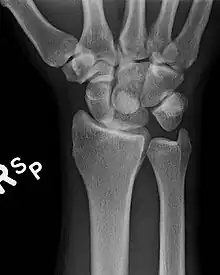

Dislocated lunate